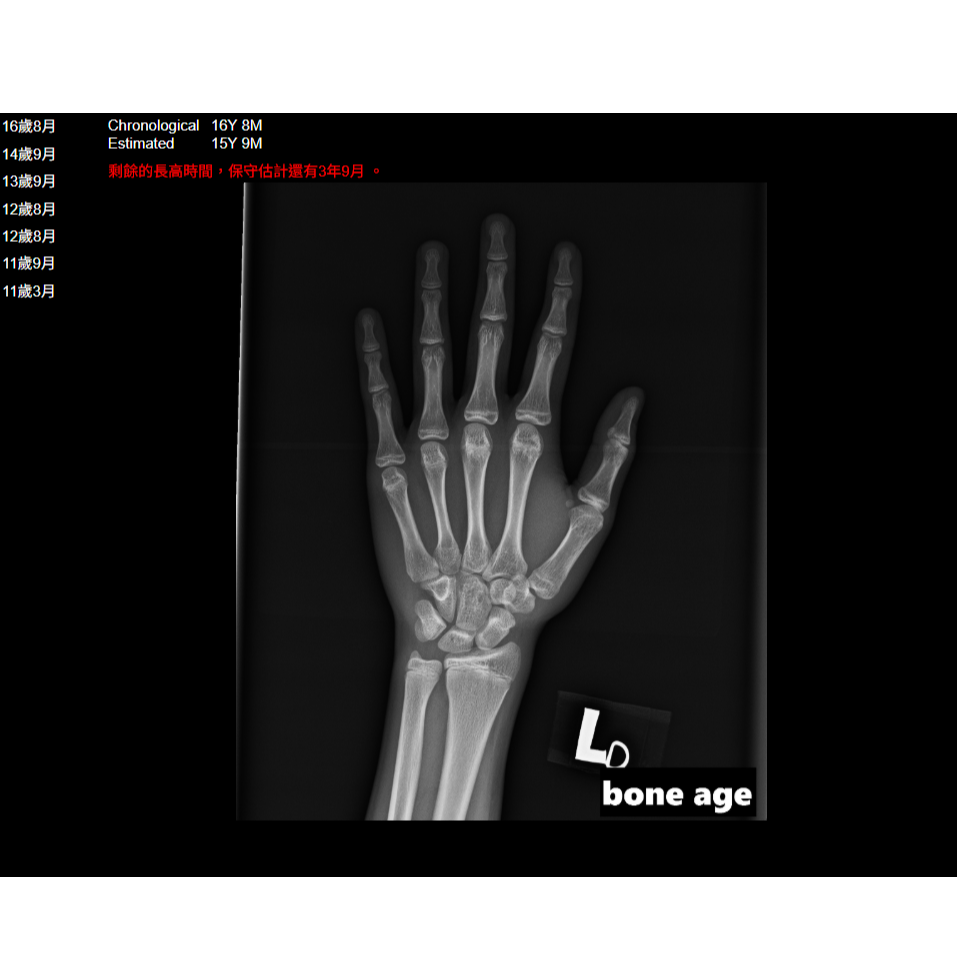

只要是長骨的部分 我們兩端都會有一個生長板 隨著年紀的生長 生長板它也會慢慢的變成熟 到青春期的時候 生長板會從軟骨變成骨頭 腕骨化 那這個時候就定型了 那骨齡是過去50年前歐美的一個學者 他們去收集不同年紀的小孩子手掌的X光 去看手指的指...

諮詢的病人來到我們這邊,需要做的檢驗項目是非常全面的,第一個是最基本的抽血檢查,抽血的內容包括,過敏的反應、營養素的缺乏一些注重的地方,一些運動醫療抽血的過程,再來會幫大家照X光,骨齡的檢查,透過這些檢查達到最需要跟最適合的療程。

病人到我們諮詢處,第一個會透過諮詢師先瞭解病歷初初診的狀況,再來會透過電腦讓病人瞭解整個療程的方向,還有AI的系統,和未來會找到一些相關文章參考的地方,接著透過專業醫師的問診,護士幫忙抽血完之後,做一個X光,骨齡的測試照射後,我們會在下個月...

首先我們來談一下,長高的小朋友需要定期做哪一些醫療檢查項目,其實如果你發現家中的小朋友,他的生長曲線不如預期,例如說跟其他同齡的小朋友覺得他長得比較矮小的時候,我們會建議他定期來做一些醫療檢查,其中包括像一些血液的檢查,或是尿液檢查,那血液...